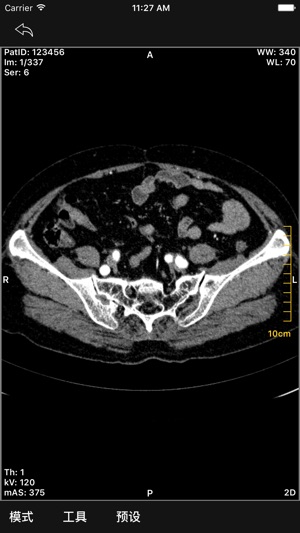

- 2D图像显示

- 图像交互:放缩,平移,选择,窗宽窗位调节等